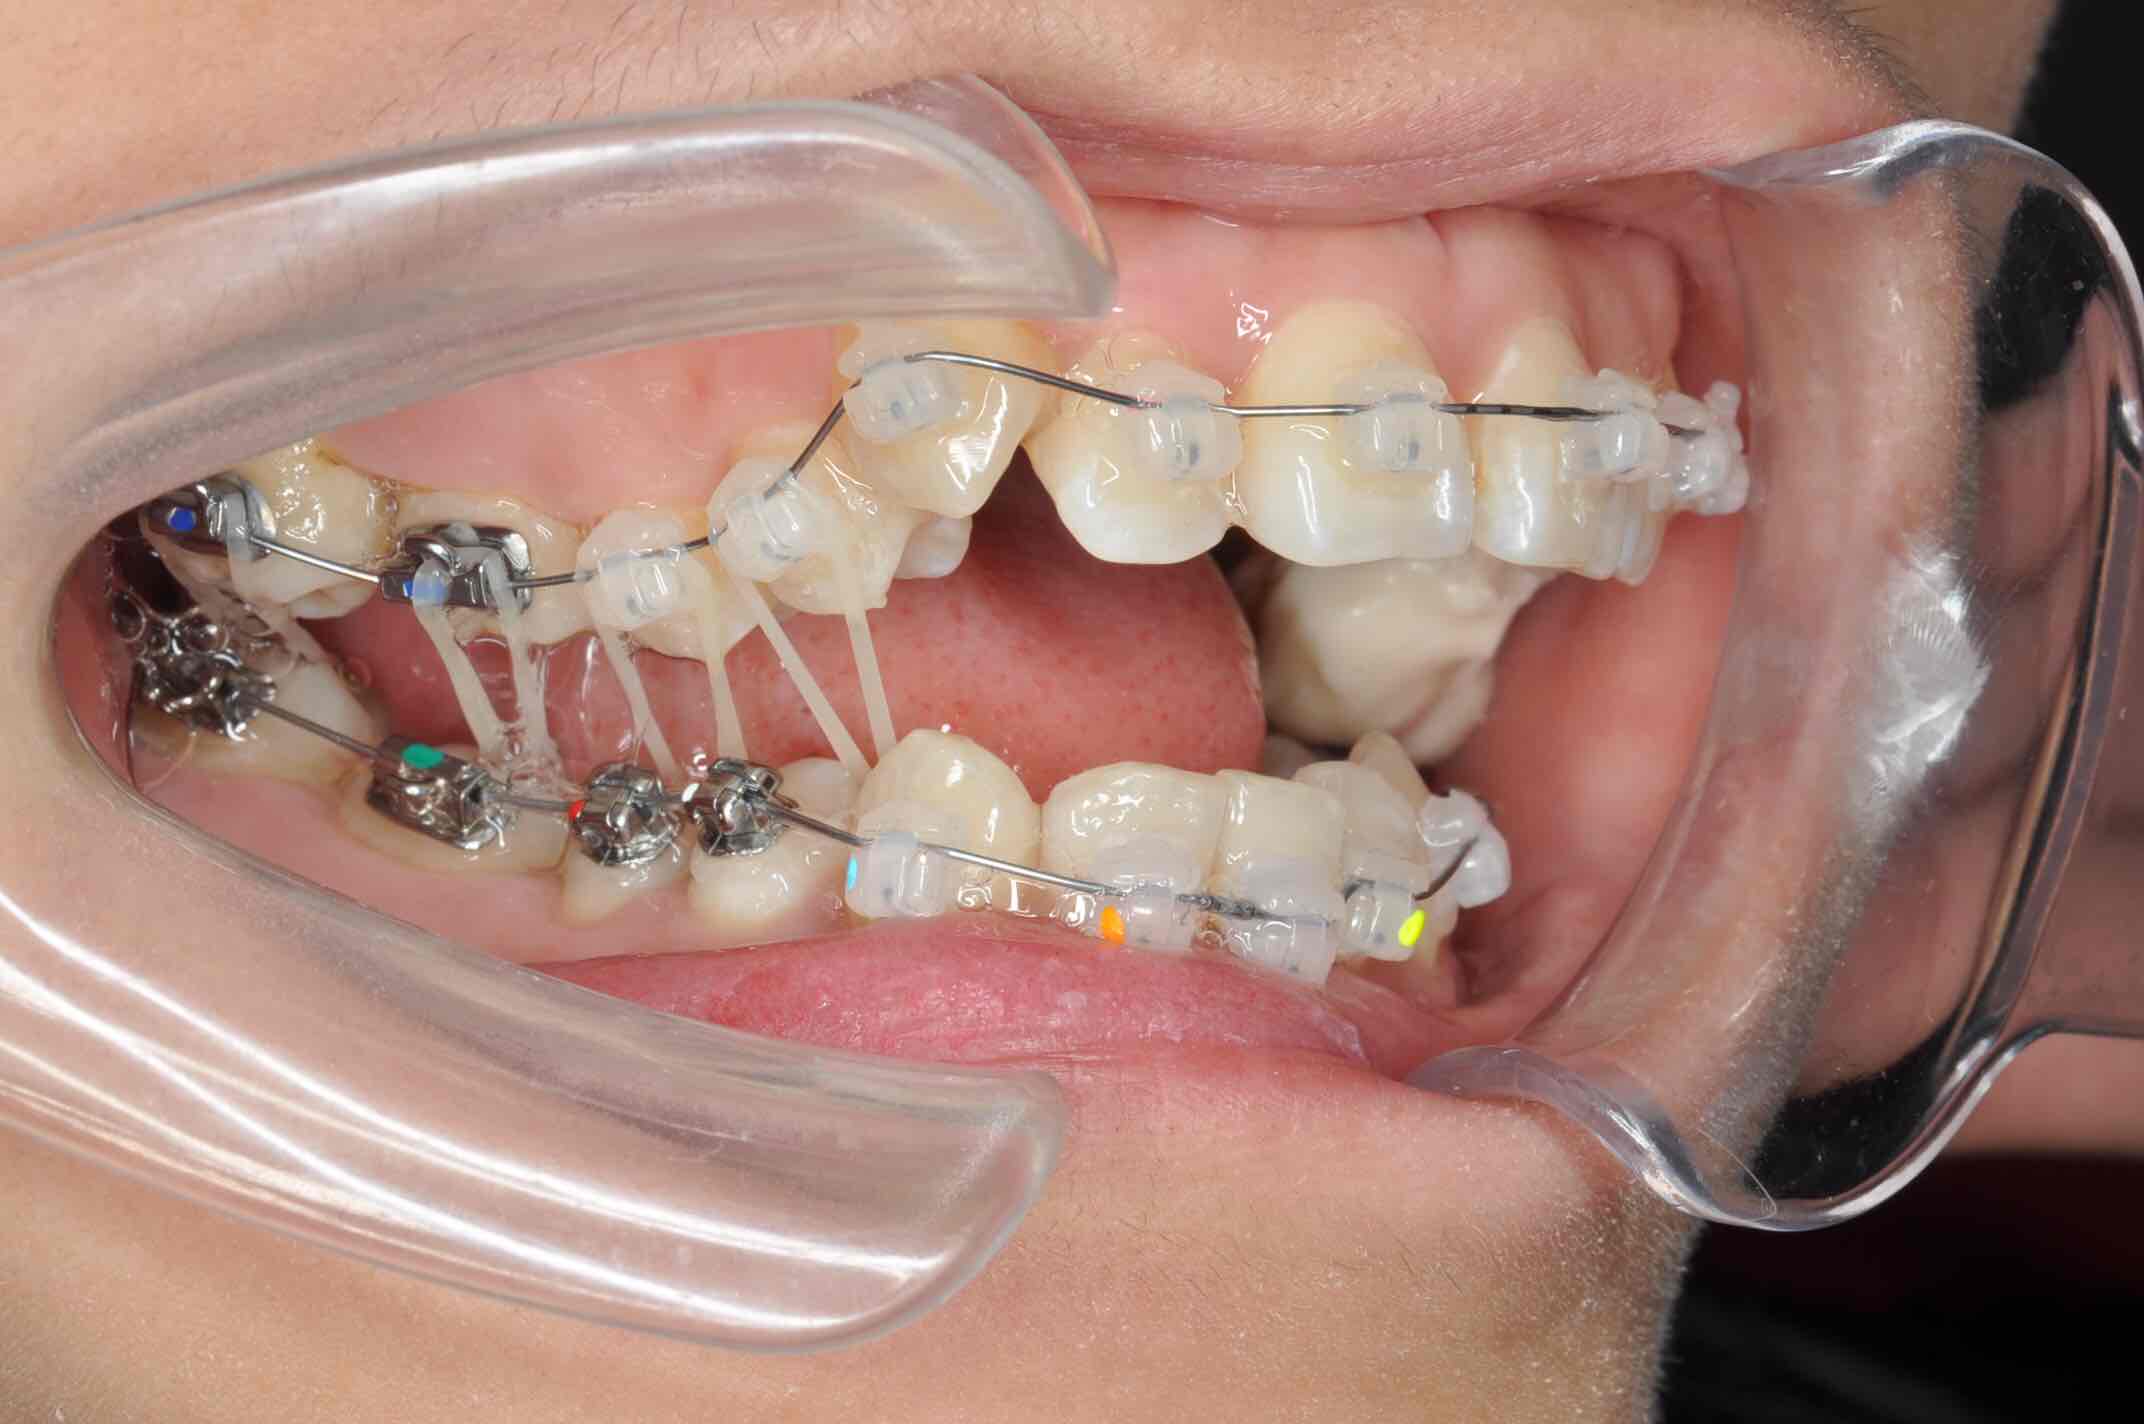

矫正中解决锁合

矫正中解决锁合

矫正中解决锁合